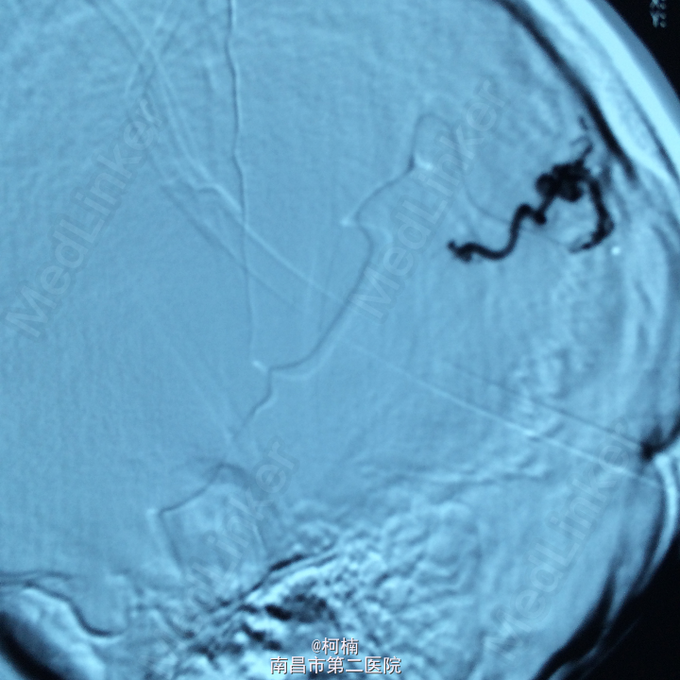

诊断:脑动静脉畸形 处理:予急诊行DSA检查,提示脑动静脉畸形,予行血管内栓栓塞治疗

随访:患者术后恢复良好。 讨论:关于脑动静脉畸形的治疗,有:1.手术治疗,现多采用显微神经外科技术切除病变血管团,单纯结扎供血动脉易复发,现已不主张采用。合并颅内血肿者须紧急手术,可能时同时切除病变。2.血管内栓塞治疗,对病变深在,位于重要功能区或高血流病变,宜行栓塞治疗。单纯栓塞治疗只能治愈一小部分病变,可在部分栓塞后再行显微手术切除。3.立体定向放射外科治疗,即X刀或γ刀,无创伤,但价格昂贵,显效慢,适用于深部直径小于3cm病变或手术与栓塞后残余病变。